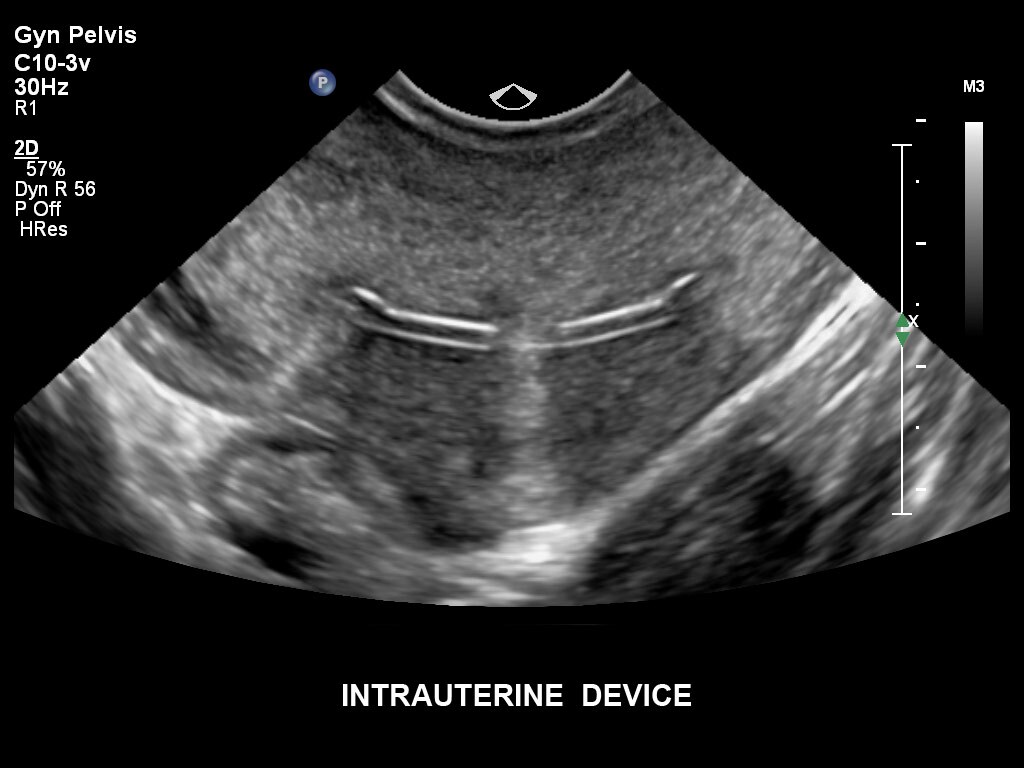

Die EPIQ-Produktreihe mit ausgereiften Schallköpfen erfüllt die Anforderungen auch Ihrer anspruchsvollsten gynäkologischen Untersuchungen und während der gesamten Schwangerschaft.

• C10-3v PureWave-Breitband-Endo-Convex-Schallkopf, ideal für anspruchsvolle Myom- und komplexe Ovar-Untersuchungen sowie Bildgebung im ersten Schwangerschaftstrimester